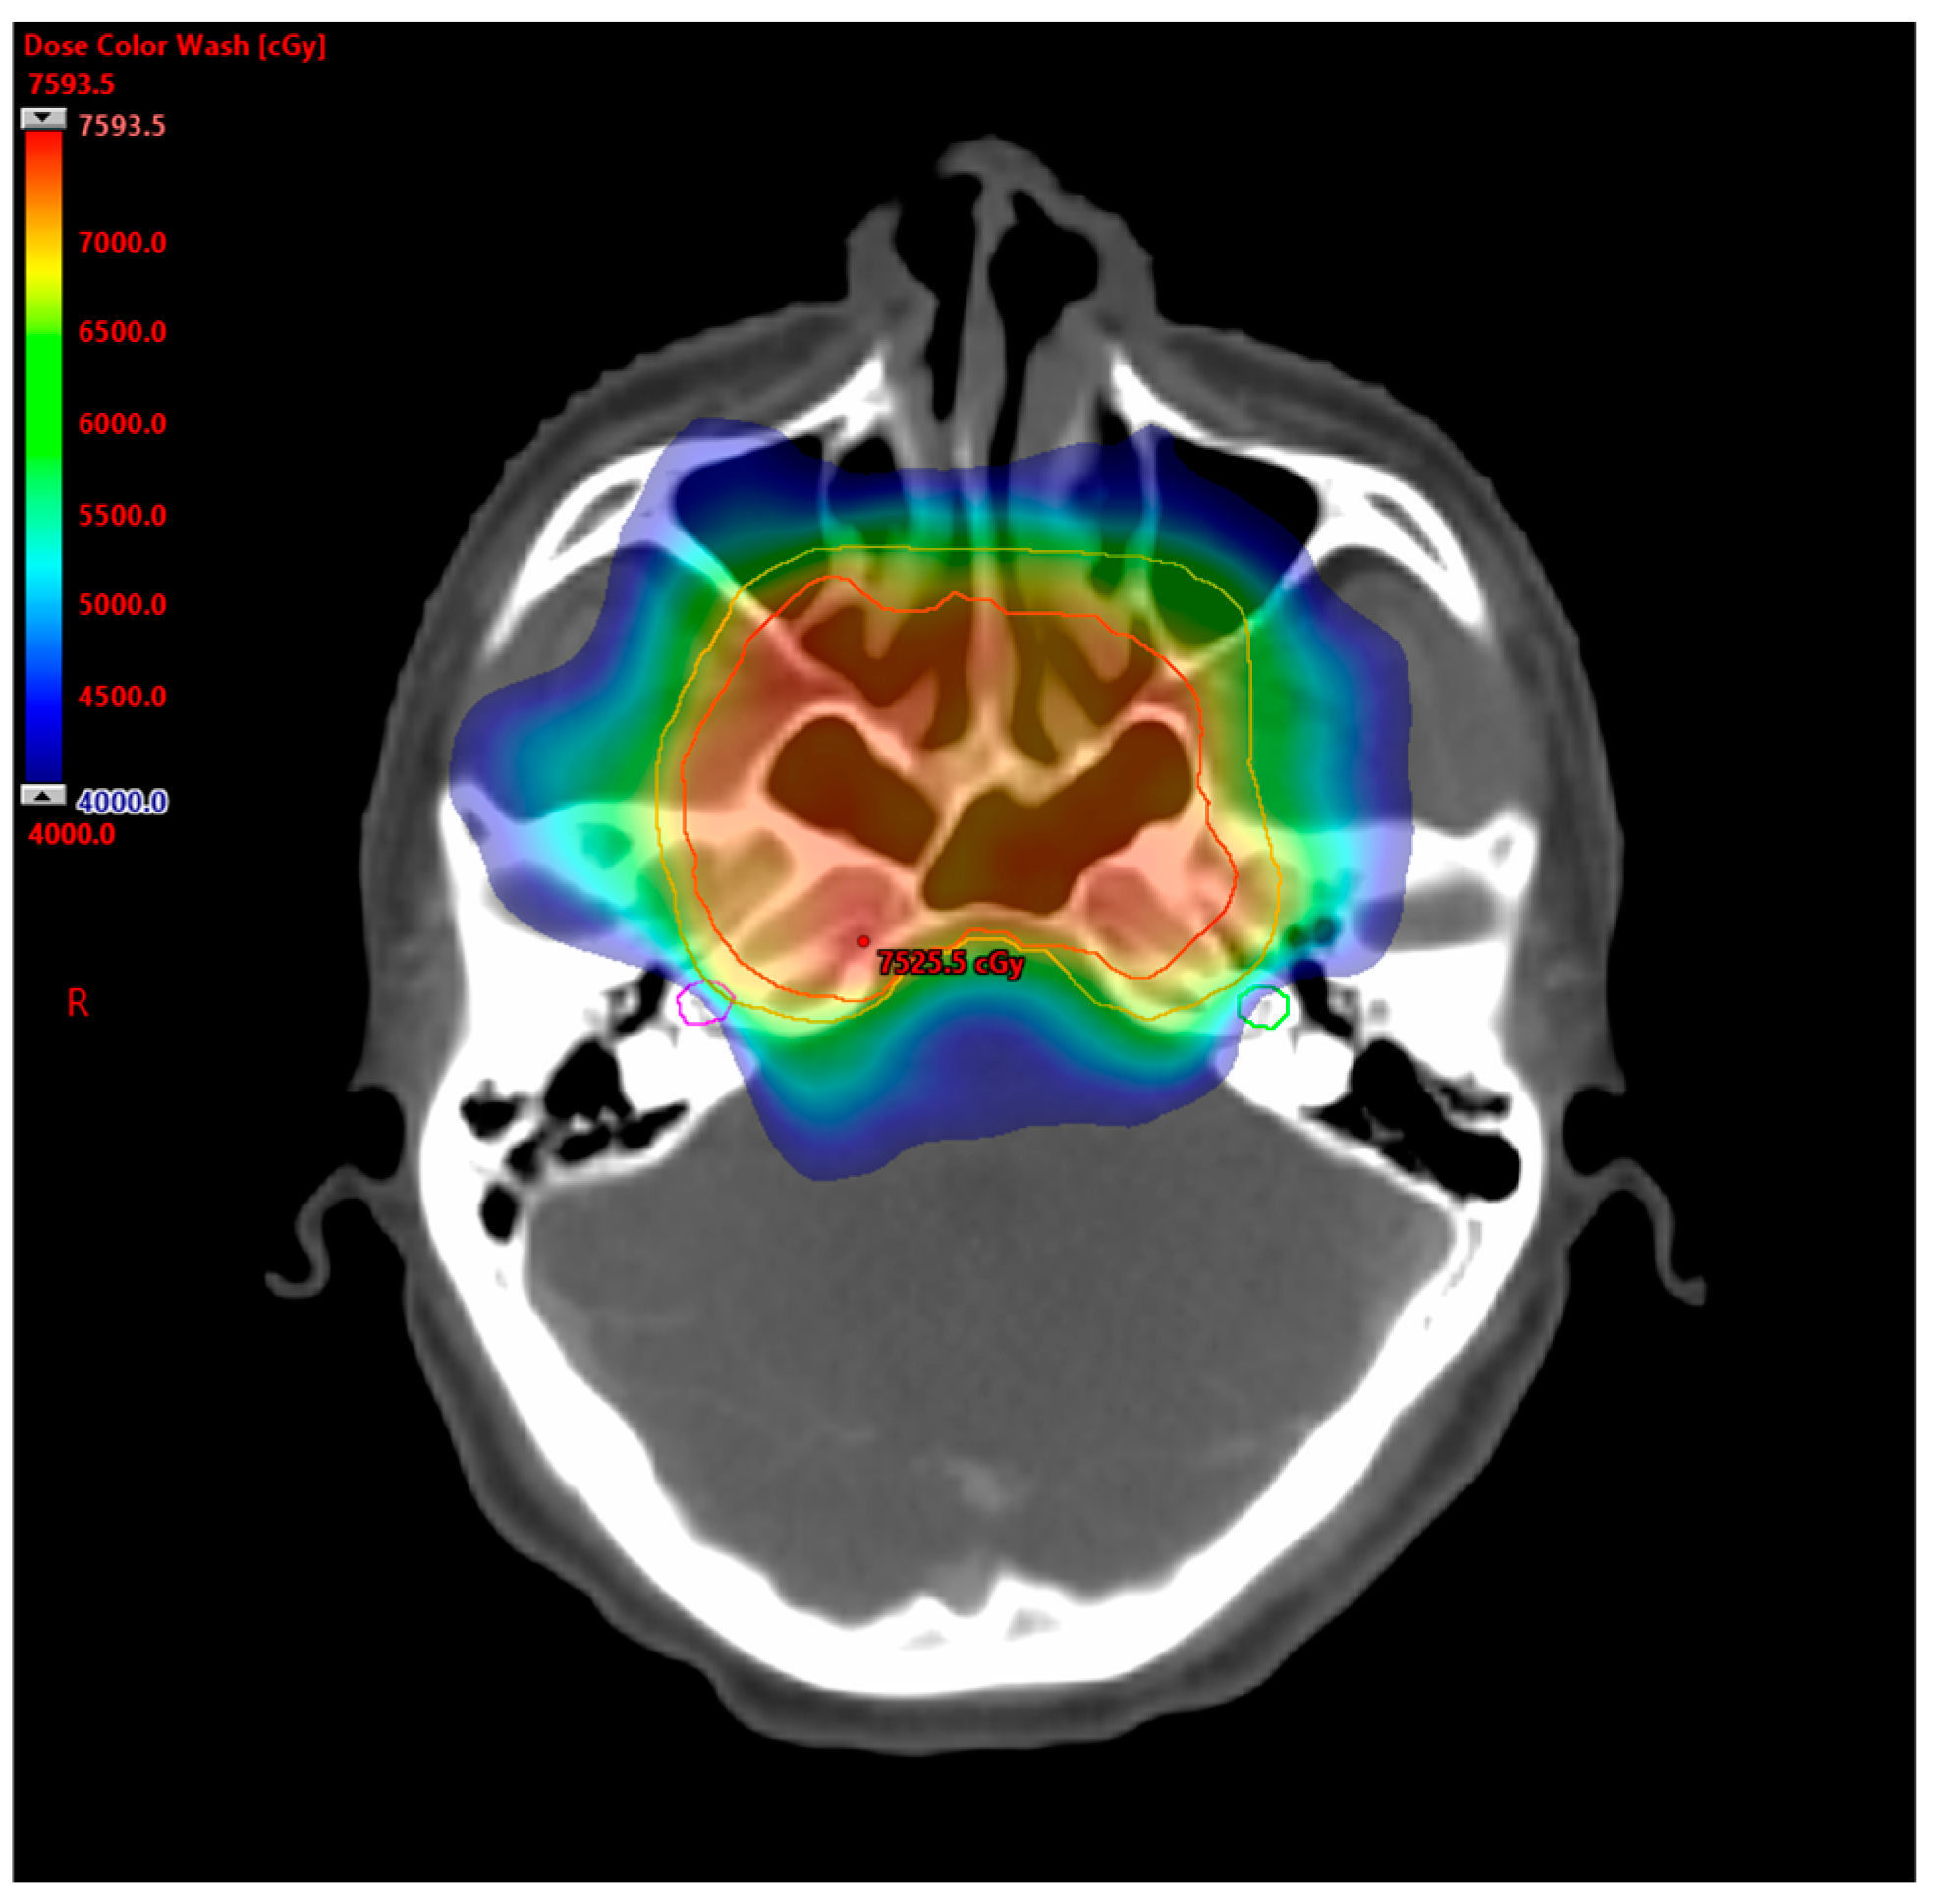

4.3. Selection of Radiotherapy Techniques